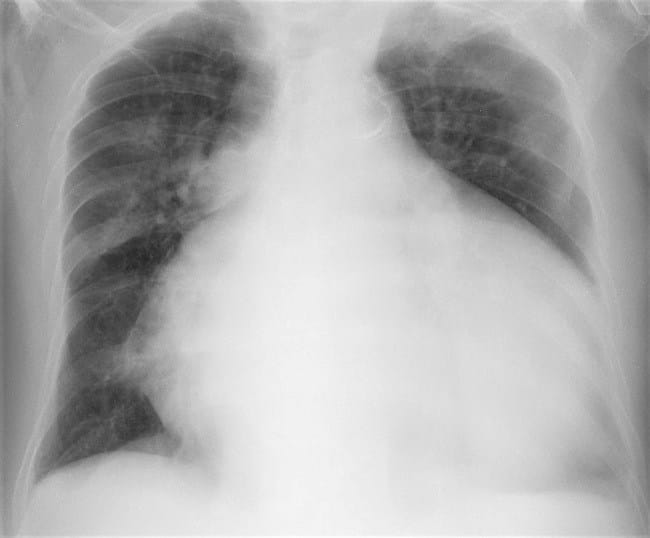

Kardiomegali dapat terlihat melalui pemindaian gambar, seperti foto Rontgen. Kondisi ini umumnya bukan merupakan suatu keadaan darurat. Namun, penting untuk mencari tahu penyebab kardiomegali sehingga penanganan yang tepat bisa diberikan dan komplikasinya dapat dicegah.

- Foto Rontgen dada, untuk melihat ukuran jantung dan paru-paru